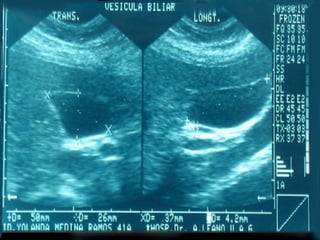

SONOGRAMA ABDOMINAL EVACUACIÓN VESÍCULA BILIAR Estructura elongada, ovoide Pared bien definida, no debe superar los 3 mm. De grosor. Longitud 7 -10 cm. (menos de 13 cm.) Diámetro  3 cm. ( < 4 cm. )

SONOGRAMA ABDOMINAL EVACUACIÓNVESÍCULA BILIAR Estructura elongada, ovoide Pared bien definida, no debe superar los 3 mm. De grosor. Longitud 7 -10 cm. (menos de 13 cm.) Diámetro 3 cm. ( < 4 cm. )